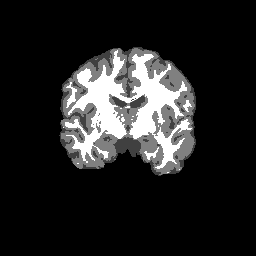

Overlap coefficients for each tissue class are shown here for each IBSR subject. Select a subject below to see the FSL results compared to other tools.